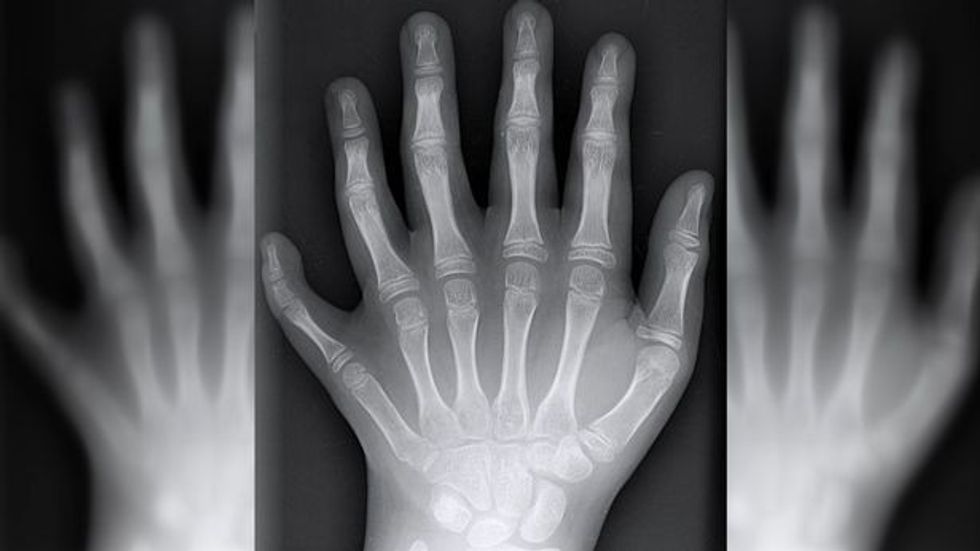

Familja 14 anëtarëshe që ka nga gjashtë gishta, i urojnë mirëseardhje në këtë botë anëtarit më të ri të familjes që ka të njëjtin sindromë gjenetike (Foto/Video)

Një familje 14 anëtarëshe ku secili prej tyre ka lindur me nga gjashtë gishta në duar e këmbë, i kanë uruar mirëseardhjen në këtë botë anëtarit më të ri të familjes, i cili ka trashëguar të njëjtin “çrregullim” gjenetik.

Ky sindrom gjenetik që i bën njerëzit të lindin me nga gjashtë gishtërinj në duar dhe këmbë quhet Polydactyly. Ajo prek një në një mijë persona, dhe për çudi në familjen De Silva ka prekur të gjithë. /Telegrafi/